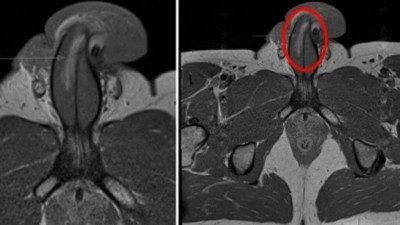

Um homem de 40 anos fraturou o seu pênis verticalmente depois que ele "dobrou" durante o sexo, disseram médicos que o atenderam. Ele sofreu uma ruptura de 3cm no lado direito do seu membro sexual e precisou ser submetido a cirurgia urgente.

Os especialistas acreditam que este é o primeiro caso registrado na História desse tipo de lesão, já que todos os casos anteriores de fratura peniana relatados foram horizontais.

Embora não haja ossos no pênis, a genitália pode parecer estar se quebrando após um traumatismo contuso. O órgão pode entortar e dobrar sob muita pressão, fazendo com que o sangue vaze. Os médicos, que compartilharam suas descobertas na revista "British Medical Journal", disseram que nenhum "som de estalo" foi ouvido, o que acontece durante fraturas horizontais.